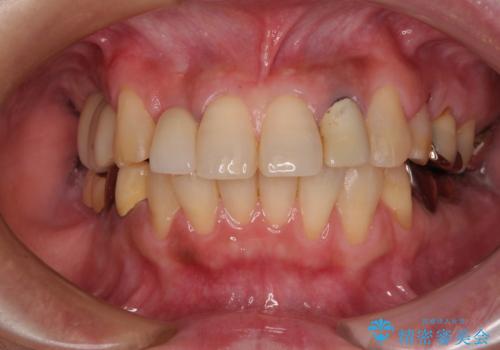

隙間の空いた歯列とボロボロの乳歯 インプラント治療と矯正治療

- 隙間の多い歯列や傾斜した奥歯、むし歯の酷い残存乳歯を気にして来院された患者様です。

歯列はワイヤー矯正にて改善することとしましたが、上下歯列にも隙間があったので、舌の突出癖を改善するトレーニングを徹底的に行うこととしました。

傾斜した下顎の奥歯は、矯正治療にてまずは歯軸を改善させ、隙間が閉じられるようであればそのままに、閉じられないようであればインプラント治療を行うこととしました。

上顎のむし歯の酷い残存乳歯は抜歯をし、矯正治療の途中でインプラントを埋入、矯正治療後に補綴治療を行うこととしました。